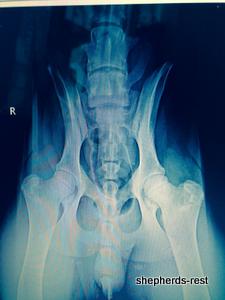

Sırtlan's hip x-rays in Turkey July 2014